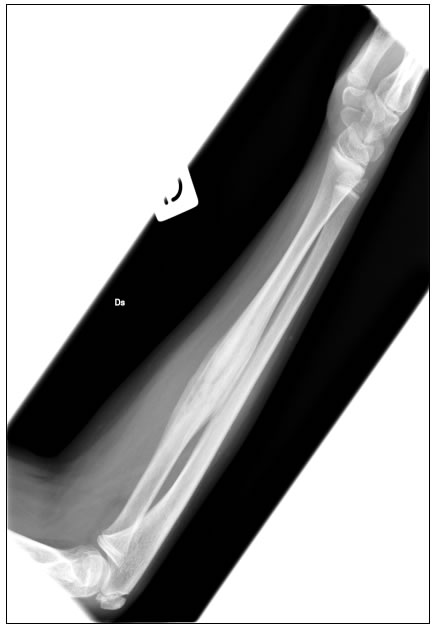

Il successivo decorso clinico si caratterizza per la comparsa di dolori agli arti superiori, con evidenza di lesioni radiografiche di osteite-iperostosi disreattiva multifocale (figura 5).

La ragazza � stata posta in trattamento per pochi mesi con apparente risultato iniziale, ma successivamente nonostante le infusioni la malattia riprende con dolori e un marcato peggioramento del quadro radiografico della sola lesione radiale destra (reazione periostale significativamente aumentata rispetto all'esame eseguito precedentemente, (figura 6) rendendo necessario l'avvio di un ciclo di steroide.

Figura 5: il radiogramma dell'avambraccio mostra una zona di alterazione della struttura ossea a livello del radio, in gran parte osteoaddensante, con piccole aree di rarefazione nel contesto.

Figura 6: reazione periostale significativamente aumentata rispetto all'esame eseguito precedentemente